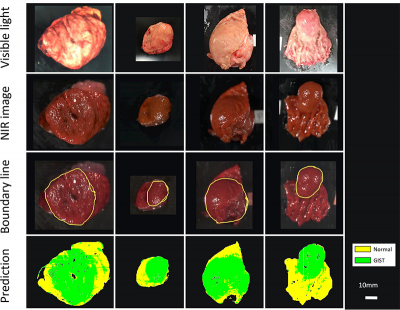

The team, led by Dr Hiroshi Takemura from Tokyo University of Science, performed imaging experiments on 12 patients with confirmed cases of GISTs, who had their tumours removed through surgery. The scientists imaged the excised tissues using NIR-HSI, and then had a pathologist examine the images to determine the border between normal and tumour tissue. These images were then used as training data for a machine-learning algorithm.

They found that even though 10 out of the 12 test tumours were completely or partly covered by a mucosal layer, the machine-learning analysis was effective in identifying GISTs, correctly classifying tumour and non-tumour sections with 86 % accuracy. “This is a very exciting development”, Dr Takemura explains, “being able to accurately, quickly and non-invasively diagnose different types of submucousal tumours without biopsies, a procedure that requires surgery, is much easier on both the patient and the physicians.”